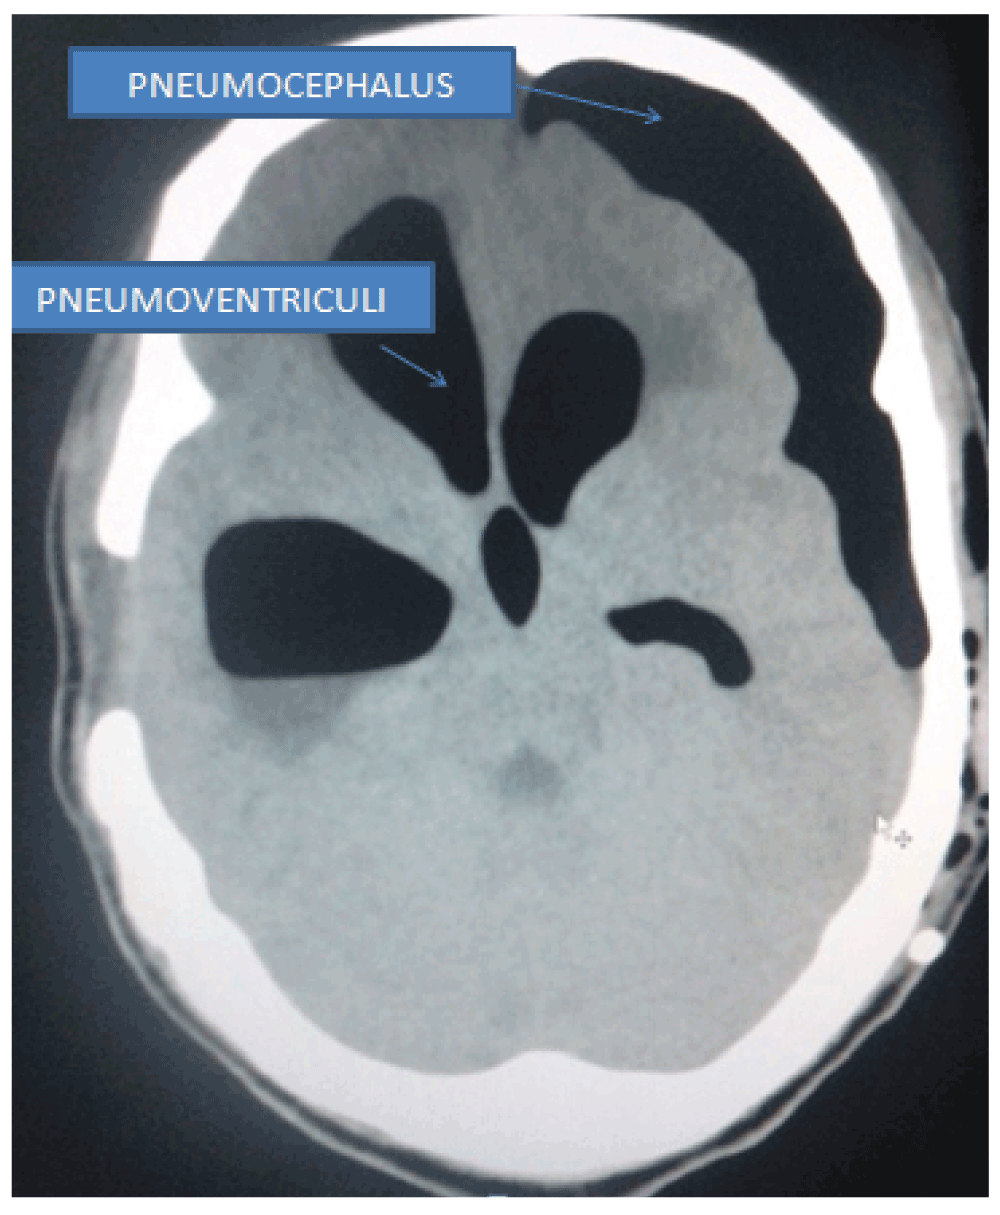

A postoperative scan revealed the presence of tension pneumocephalus and pneumoventriculi (Figure 1 and Figure 2). The patient was managed with 100% oxygen for 3 days and was continued on antiepileptic medications at the same dose intravenously. Stringent neurological monitoring was undertaken to evaluate early neurological deterioration due to tension pneumocephalus. Pupils were routinely assessed to look for hippus (a clinical marker of epilepsy). Patient was extubated the following morning. A repeat CT scan on the 6th day post-operation showed that the proximal shunt was in the third ventricle (Figure 3) and there was complete resolution of the condition. The EVD was subsequently removed with no neurological deterioration of the patient on 7th day after operation. The patient then started to walk with support from the 8th day post-operation, and he slowly improved in gait. Patient went home walking with minimal support on the 14th day post-operation. Patient had also regained his bladder control within that time. Patient returned, walking on his own 1 month later for his follow up in the outpatient department His gait was normal with no features of retropulsion. The shunt chamber was functioning well and his bowel habits were normal. Compliance in continuation of Sodium valproate therapy (at the aforementioned dose) was also ensured.

Figure 1. CT image showing presence of pneumocephalus and pneumoventriculi.